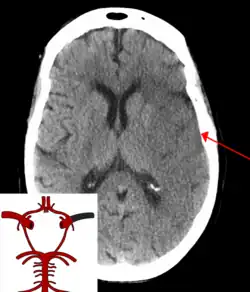

CT scan of the brain showing a massive, prior right-sided ischemic stroke from blockage of an artery. Changes on a CT may not be visible early on.[1]

A CT showing early signs of a middle cerebral artery stroke with loss of definition of the gyri and grey white boundary

Dense artery sign in a patient with middle cerebral artery infarction shown on the left. Right image after 7 hours.

Stroke is diagnosed through several techniques: a neurological examination (such as the NIHSS), CT scans (most often without contrast enhancements) or MRI scans, Doppler ultrasound, and arteriography. The diagnosis of stroke itself is clinical, with assistance from the imaging techniques. Imaging techniques also assist in determining the subtypes and cause of stroke. There is yet no commonly used blood test for the stroke diagnosis itself, though blood tests may be of help in finding out the likely cause of stroke.[76] In deceased people, an autopsy of stroke may help establishing the time between stroke onset and death.

CT scans may not detect ischemic stroke, especially if it is small, of recent onset,[10] or in the brainstem or cerebellum areas (posterior circulation infarct). MRI is better at detecting a posterior circulation infarct with diffusion-weighted imaging.[79] A CT scan is used more to rule out certain stroke mimics and detect bleeding.[10] The presence of leptomeningeal collateral circulation in the brain is associated with better clinical outcomes after recanalization treatment.[80] Cerebrovascular reserve capacity is another factor that affects stroke outcome – it is the amount of increase in cerebral blood flow after a purposeful stimulation of blood flow by the physician, such as by giving inhaled carbon dioxide or intravenous acetazolamide. The increase in blood flow can be measured by PET scan or transcranial doppler sonography.[81] However, in people with obstruction of the internal carotid artery of one side, the presence of leptomeningeal collateral circulation is associated with reduced cerebral reserve capacity.[82]